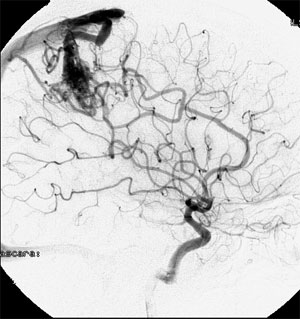

CASO 2 : Embolización combinada con Radiocirugía. Paciente con crisis convulsivas y trastorno del lenguaje. La angiografía demuestra voluminosa MAV localizada en plena área del lenguaje.

Angiografía antes de la embolización

Angiografía 7 años después de la embolización mostrando reducción importante y definitiva del volumen de la MAV, convirtiéndola en blanco óptimo para radiocirugía

Al cabo de 18 meses de la radiocirugía la MAV está curada sin efectos adversos ni secuelas. El paciente continuó su trabajo e incluso estudios de post grado.